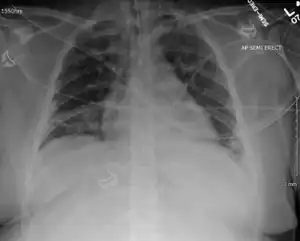

EV-D68 almost exclusively causes respiratory illness, which varies from mild to severe, but can cause a range of symptoms, from none at all, to subtle flu-like symptoms, to debilitating respiratory illness and a suspected rare involvement in a syndrome with polio-like symptoms. Like all enteroviruses, it can cause variable rashes, abdominal pain and soft stools. Initial symptoms are similar to those for the common cold, including a runny nose, sore throat, cough, and fever.[5] As the disease progresses, more serious symptoms may occur, including difficulty breathing as in pneumonia, reduced alertness, a reduction in urine production, and dehydration, and may lead to respiratory failure.[6][5]